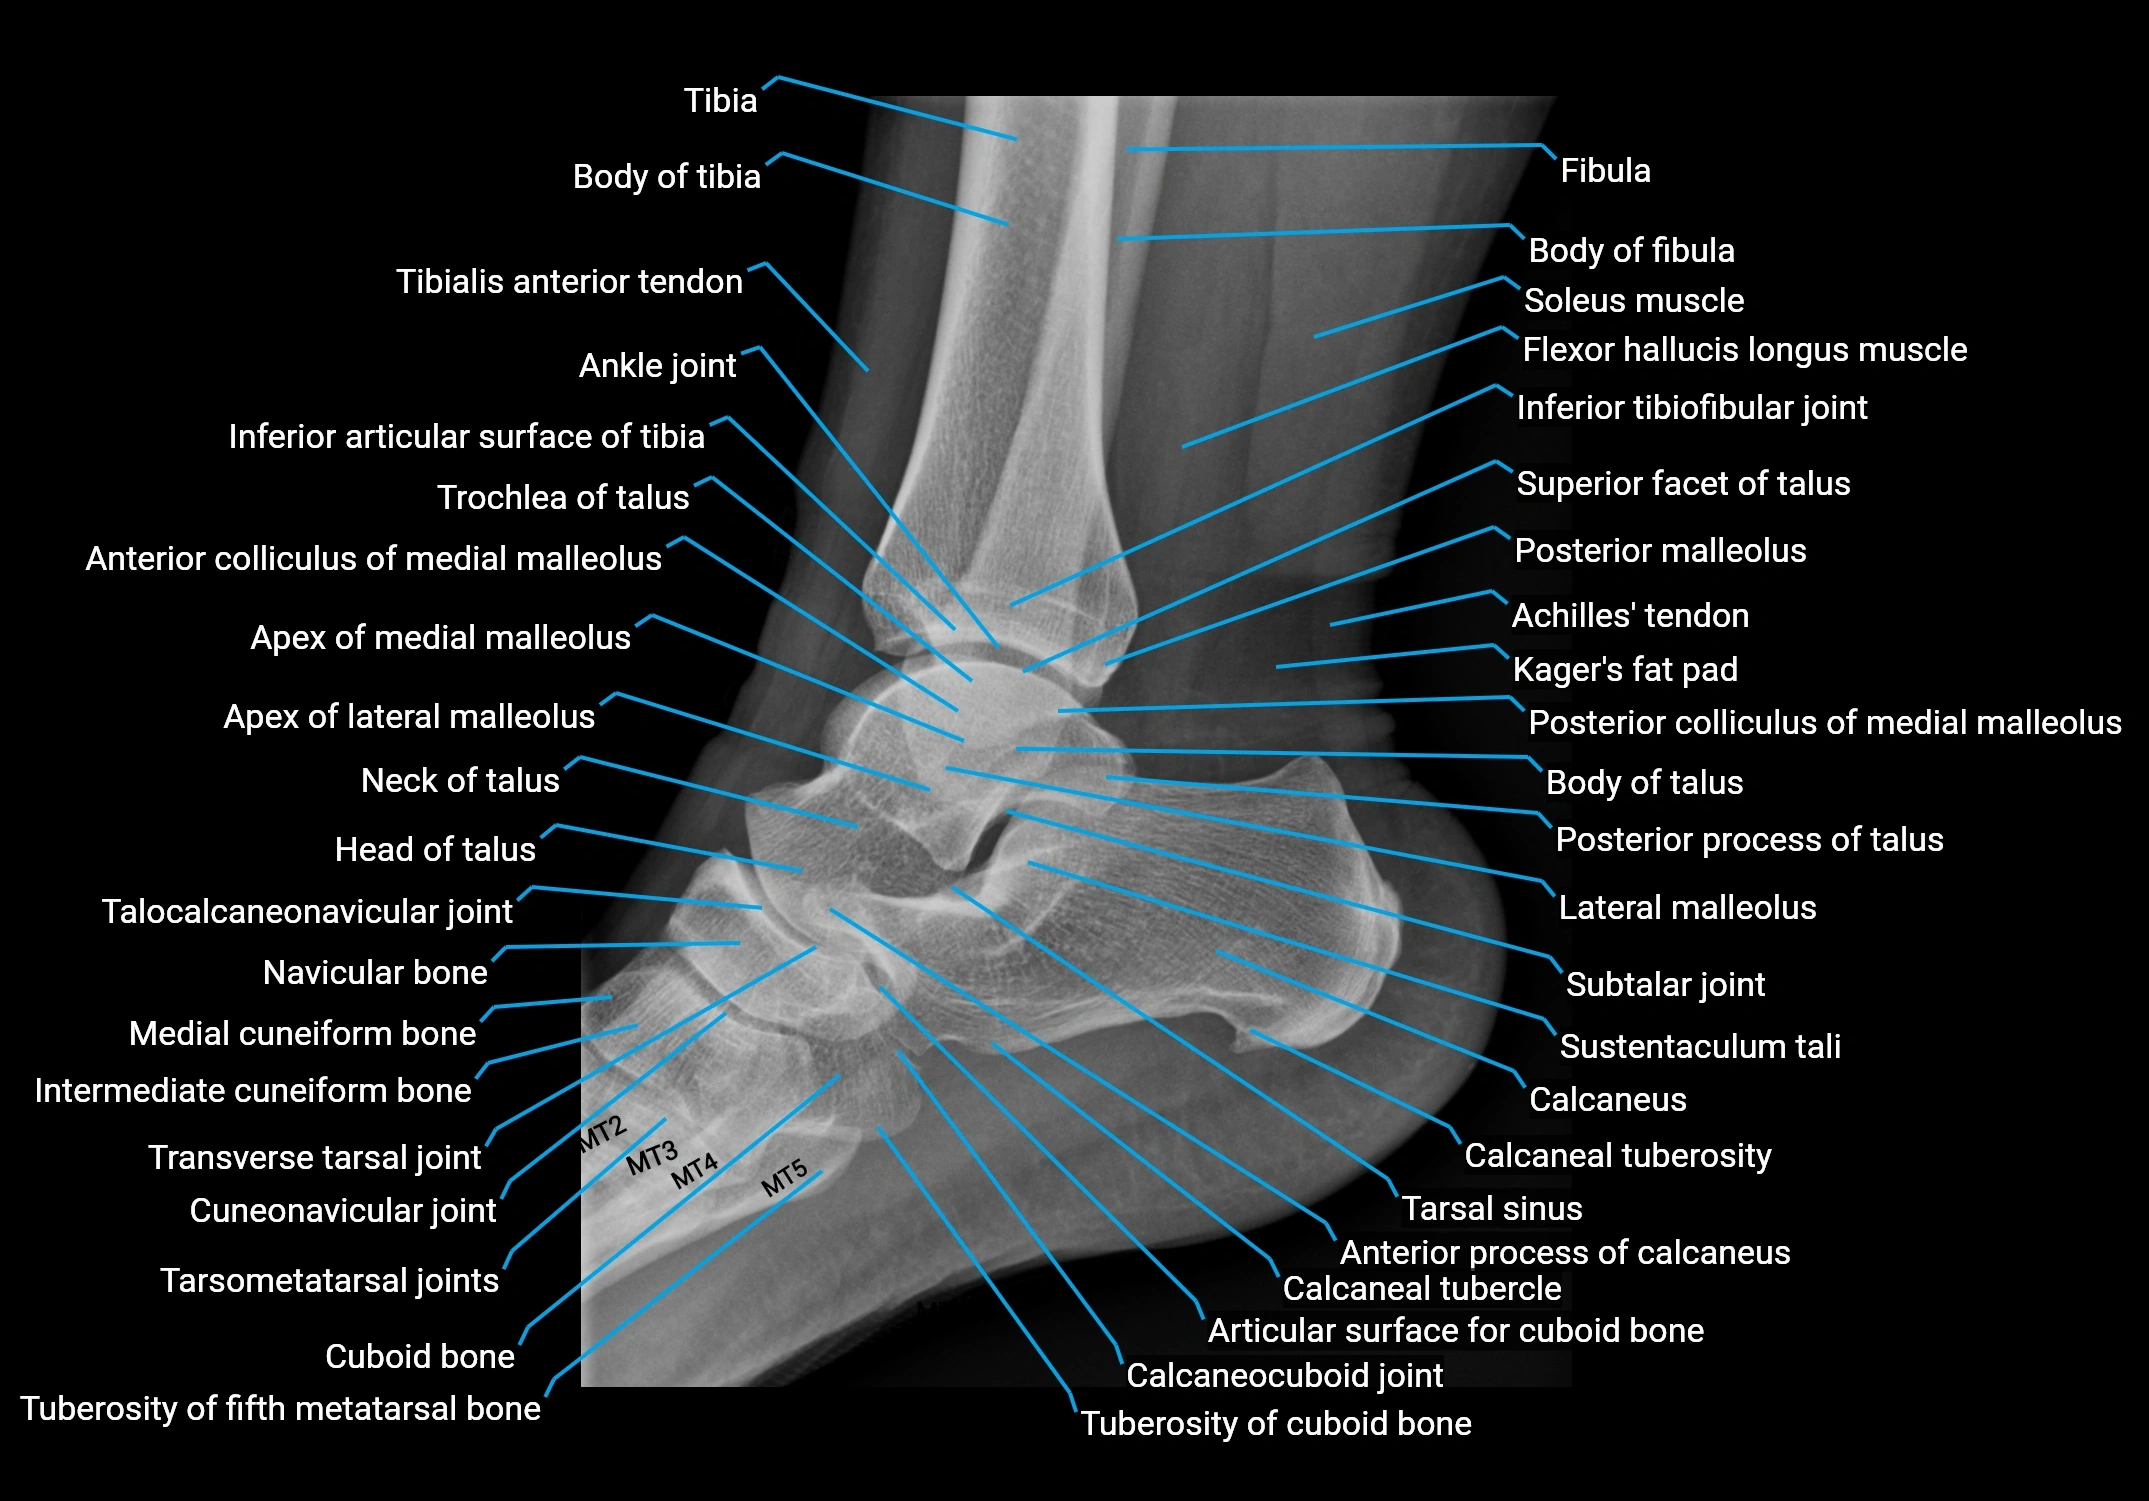

- Ankle joint

- Anterior process of calcaneus

- Articular surface for cuboid bone

- Body of talus

- Body of tibia

- Calcaneal tuberosity

- Calcaneocuboid joint

- Calcaneus

- Fibula

- Inferior articular surface of tibia

- Inferior tibiofibular joint

- Lateral malleolus

- Navicular bone

- Neck of talus

- Subtalar joint

- Superior facet of talus

- Sustentaculum tali

- Tarsal sinus

- Tarsometatarsal joints

- Tibia

- Transverse tarsal joint

- Trochlea of talus

- Tuberosity of cuboid bone

- Tuberosity of fifth metatarsal bone